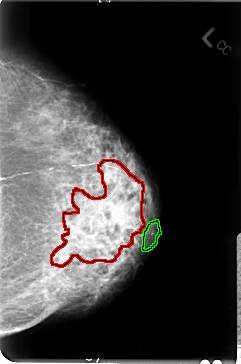

B_3027_1.RIGHT_MLO

FILE: B_3027_1.LEFT_MLO.OVERLAY

TOTAL_ABNORMALITIES 2

ABNORMALITY 1

LESION_TYPE MASS SHAPE IRREGULAR MARGINS ILL_DEFINED

ASSESSMENT 4

SUBTLETY 4

PATHOLOGY MALIGNANT

ABNORMALITY 2

LESION_TYPE CALCIFICATION TYPE PLEOMORPHIC DISTRIBUTION CLUSTERED